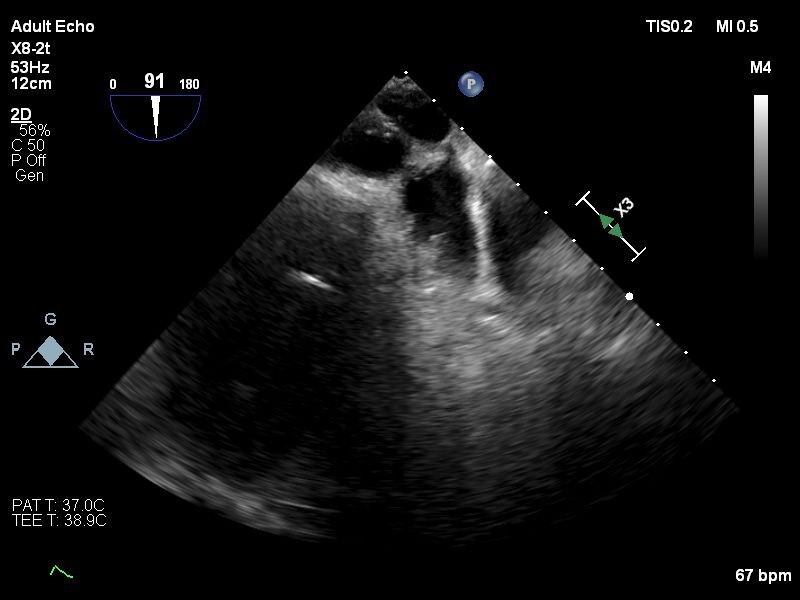

【症例】

80歳代 男性

BH: 156cm

BW: 73kg

BSA: 1.7 m2

【既往歴】

糖尿病, 高血圧症, 脂質異常症, 持続性心房細動, 食道癌, 胃癌(2020/2), 大腸癌術後(2001,2009), 慢性腎臓病, 高度貧血, TAVI(2019/12 Sapien3 26mm), 冠動脈バイバス術後(2018/04), ラクナ梗塞

しかし出血リスク高く、今回左心耳閉鎖治療予定となる